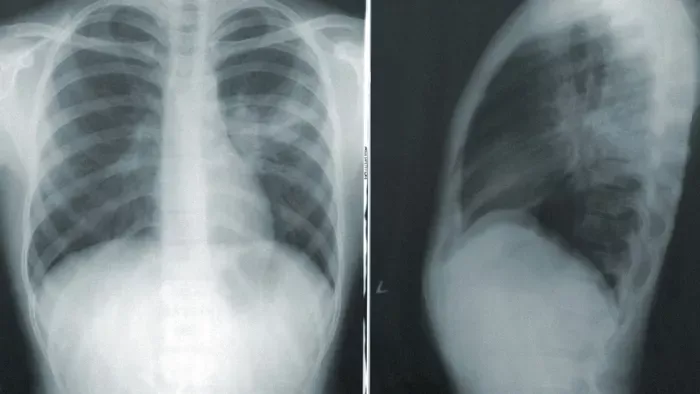

A baleset után a gyermeket a szülők a karánsebesi kórházba szállították, ahol a sürgősségi osztály munkatársainak sikerült újraéleszteniük, majd nem sokkal ezután helikopterrel szállították a temesvári kórház gyermeksürgősségi osztályára.

Mivel a kicsi a kezdetektől kómában volt, az orvosok nem sok esélyét látták annak, hogy életben marad. Végül péntek délelőtt feladta az életért folytatott küzdelmet - írja a Maszol.ro.